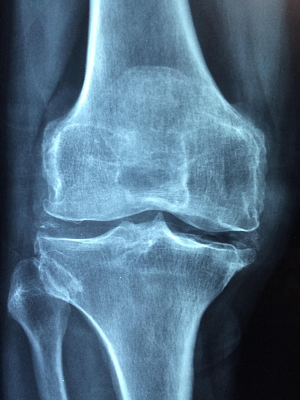

관절이 아프기 시작하면 많은 분들이 가장 먼저 떠올리는 이유는 나이입니다. 연골이 닳아서, 퇴행성 변화가 시작돼서, 이제 어쩔 수 없다고 받아들이는 경우도 적지 않습니다. 하지만 동의보감은 관절 통증을 그렇게 단순하게 보지 않았습니다.

관절은 늙어서 망가지는 구조물이 아니라, 기혈의 흐름이 막히면서 먼저 신호를 보내는 부위라고 해석했습니다. 이 관점은 오늘날 관절 건강을 이해하는 데에도 충분히 의미 있는 시사점을 줍니다.

현대의학에서는 관절 통증을 주로 연골 손상, 염증, 근육 약화, 혈액순환 저하로 설명합니다. 언어는 다르지만 구조를 보면 동의보감의 관점과 상당히 닮아 있습니다.

으로 이어지고, 이는 곧 뻣뻣함, 통증, 움직임 제한으로 나타납니다. 즉, 동의보감에서 말한 ‘불통’ 상태가 현대의학에서는 순환 장애와 만성 염증으로 설명되는 셈입니다.